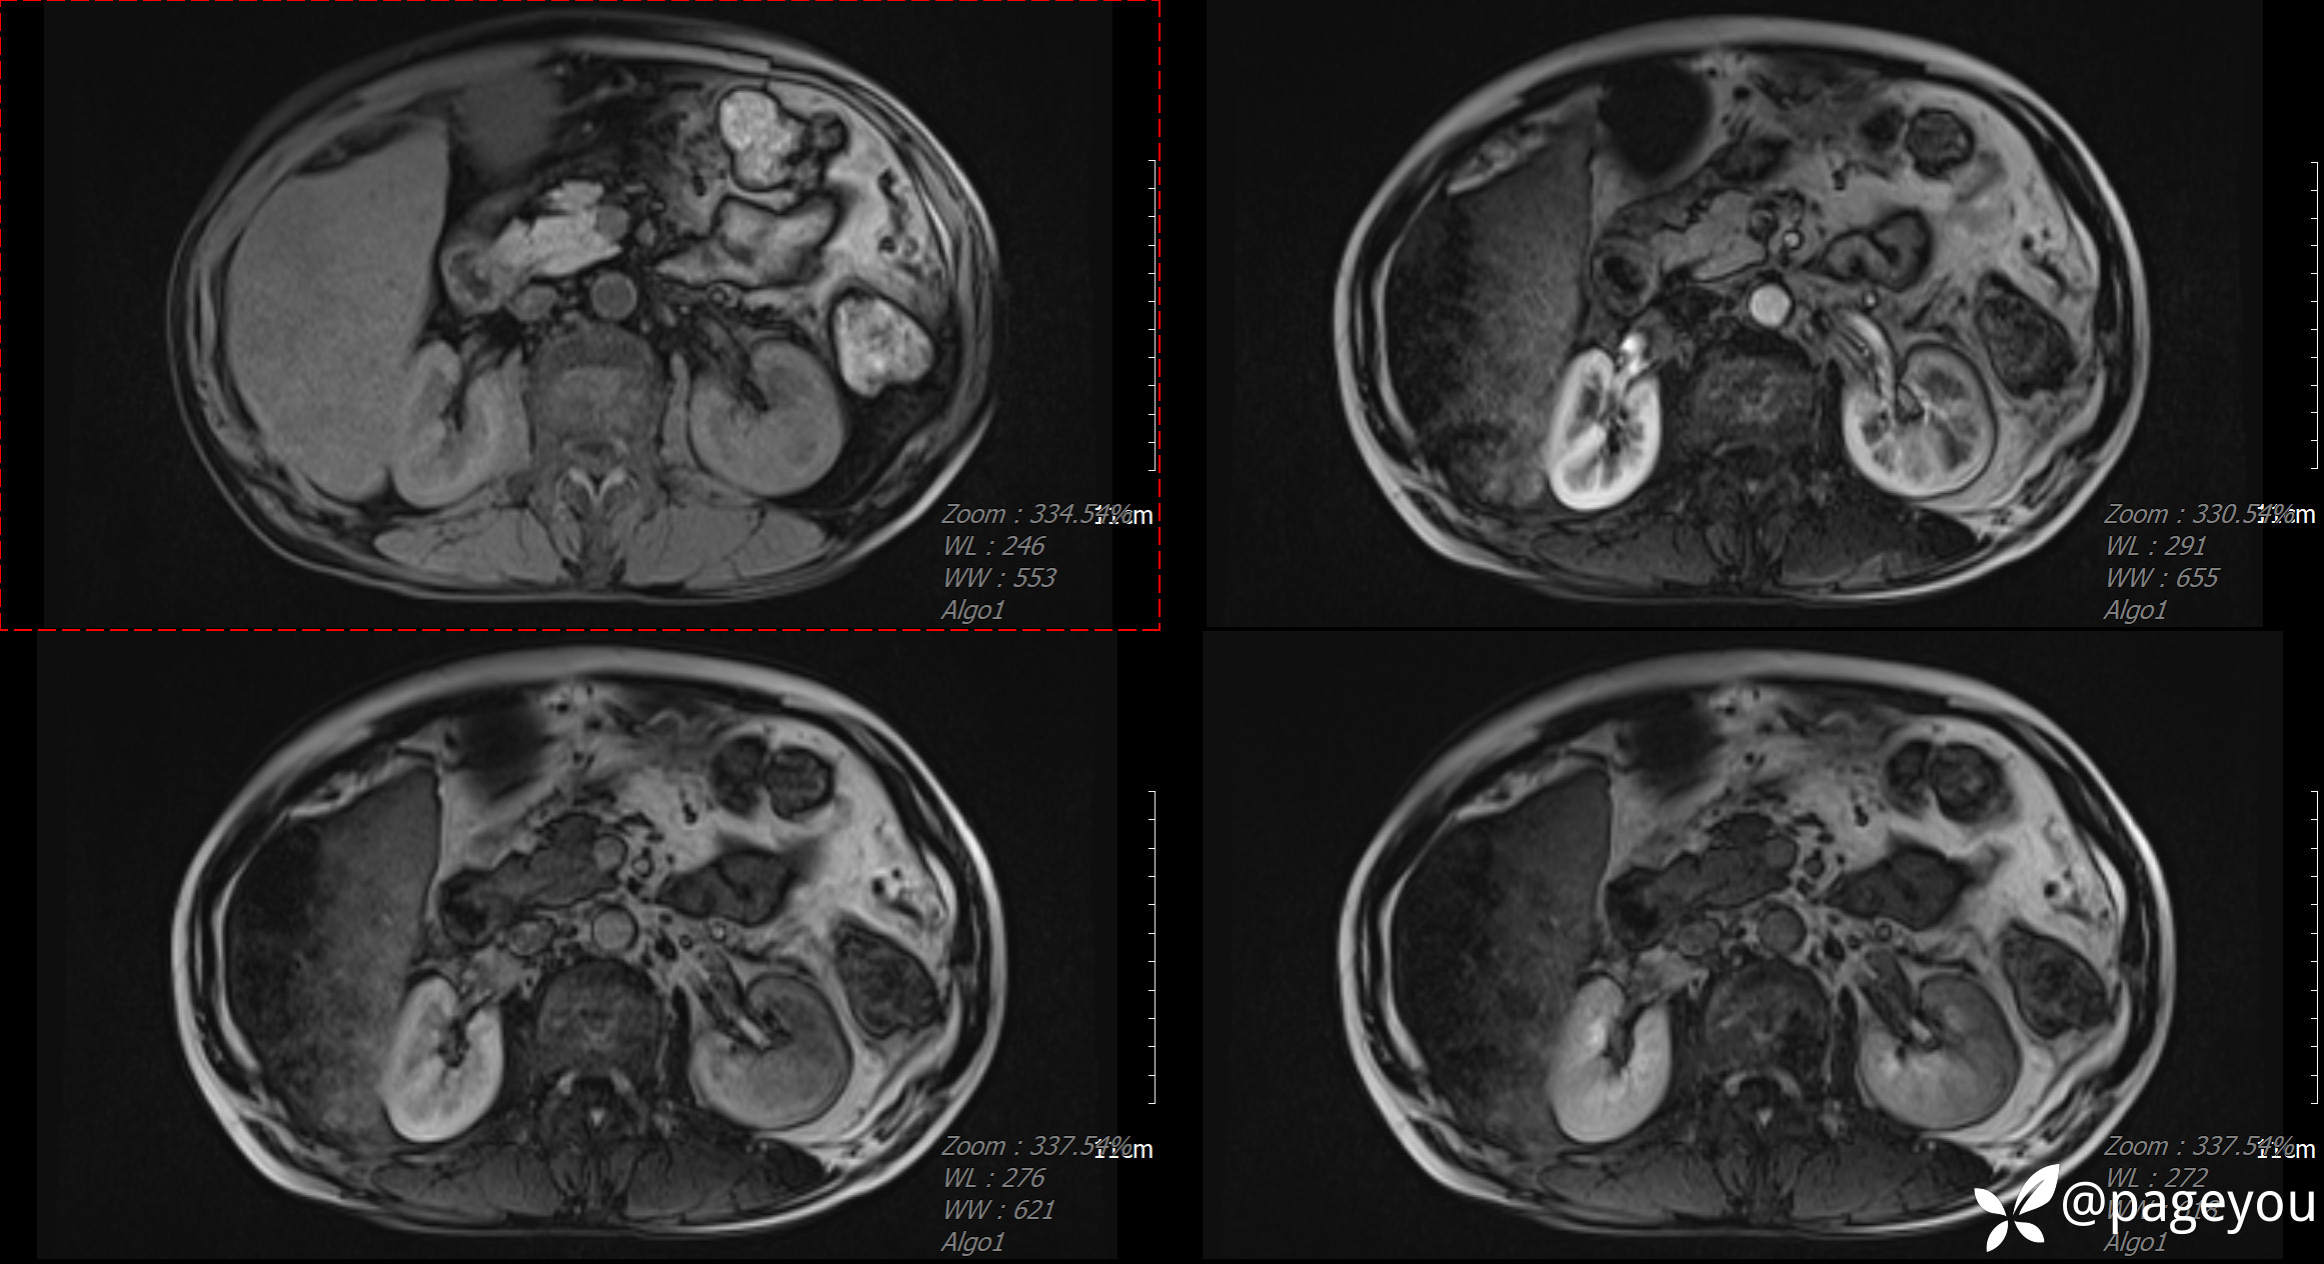

MRI检查: